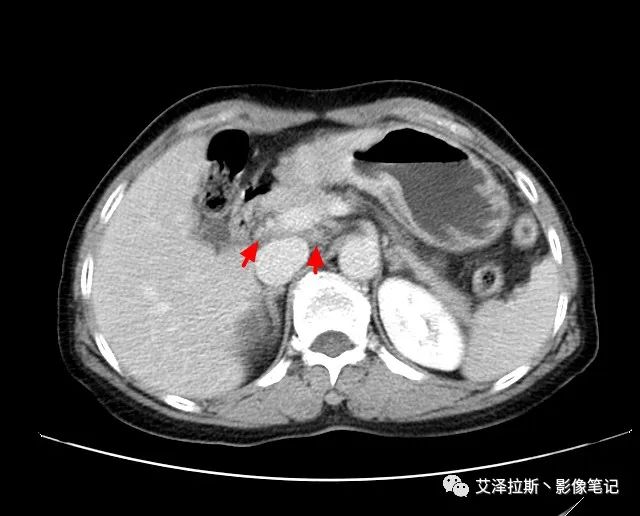

【基本情況】 患者,女性,66歲,貧血。

圖1 平掃+增強各期

【影像所見】 胃竇部狹窄,胃壁環形增厚,小彎側見一巨大潰瘍,周圍伴“環堤征”,漿膜面不完整,胃周脂肪見網格狀條索影,病灶與肝臟左葉、胰腺鉤突脂肪間隙消失,增強掃描病灶明顯強化。引流區內約15個區域淋巴結受累。

【診斷意見】 胃竇部胃癌(T4N3期) 該病例腫塊突破漿膜層,與肝臟左葉、胰腺鉤突分界不清,脂肪界面消失,定為T4期; 受累及的淋巴結為15個區域,定為N3; 有無遠處轉移尚不明確,所以M期暫時無法確定。